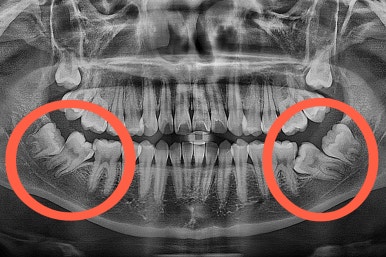

부산교정 키다리아저씨치과에 처음 내원하셨을 당시의 입안 모습과 X-ray 사진입니다.

보호자분 : "저 치아들은 사랑니 아닌가요?"

키다리 : "사랑니는 더 뒤에 또 묻혀있고, 입안에 쓰러진 채로 보이는 치아는 평생 써야 할 어금니에요."

맨 안쪽 치아가 마치 사랑니인 것처럼 누워있고 애매하게 나와있었어요.

문제는 해당 치아가 썩었다는건데, 기울어있는 치아를 제대로 치료할 방법은 사실상 없죠. 앞에 치아에 가려진 부분이 썩었으니깐요.

저대로 계속 놔두게 되면 누워있는 어금니 + 앞쪽 어금니 두 개 다 상해서 결국 뽑아야 되는 상황까지 벌어질 수 있어요. 그것도 양쪽으로 모두 다요.

하지만 이번 환자분의 경우 기울어진 치아에 사랑니가 어부바하듯이 올라탄 형태라 어금니를 당겨오는 방법도 적절하지 않은 상황이었어요.